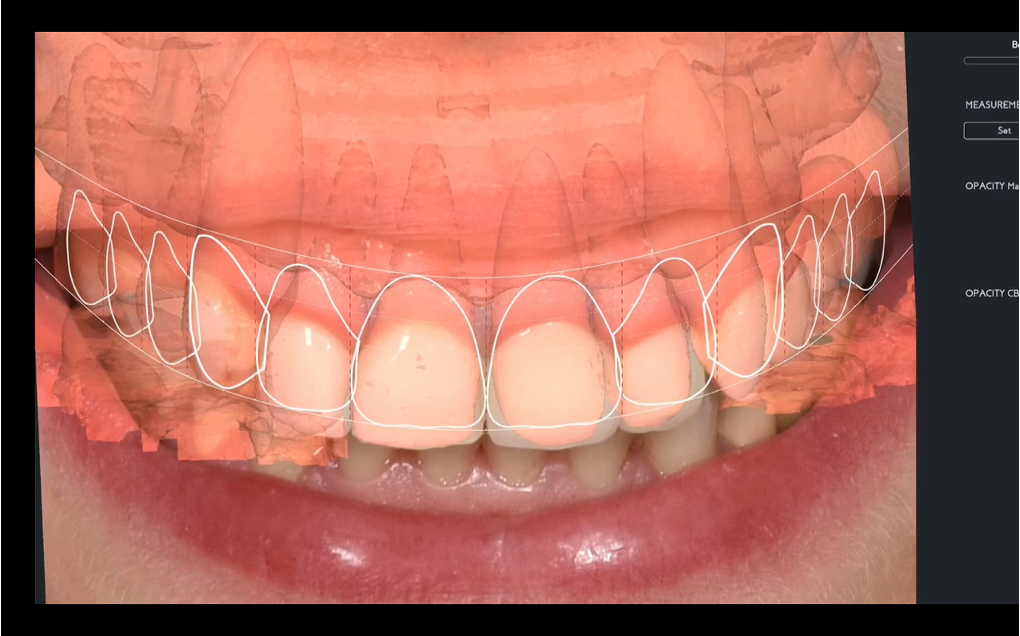

Step 1: Diagnostic Assessment and Smile Design The treatment began with a comprehensive evaluation of the patient’s smile using facially guided diagnostics. The Facial Flow Concept was employed to assess the relationship between the patient's facial structure, lips, smile arc, and gingival display. SmileFy software was utilized to generate a 2D digital smile simulation.

This visualization allowed both the clinical team and the patient to preview the planned esthetic outcome. It also provided a platform for mutual understanding and expectation management, forming a blueprint for all subsequent steps.

Step 2: Mockup Trial

Once the digital design was approved, a physical mockup was created using resin for 3Dprinted materials. This mockup served as a test-drive for the proposed outcome, enabling real-time evaluation of the smile design in terms of esthetics, speech, and occlusion. The mockup was fitted in the clinic and reviewed from multiple angles, with special attention given to the patient’s reaction and comfort. Adjustments were made accordingly, allowing for refinements before any irreversible procedures were performed.